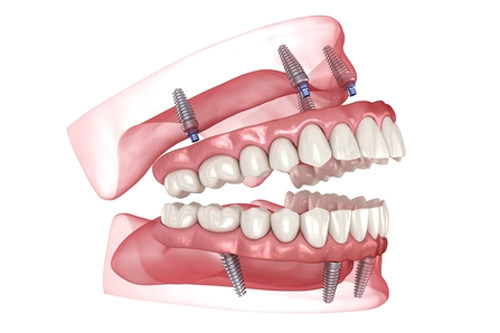

全口种植固定修复:50000-150000元